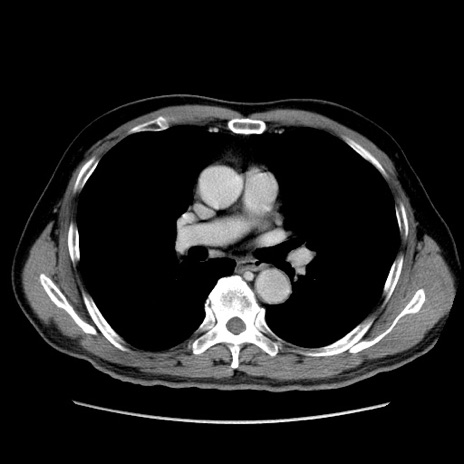

冠状断像

【症例】60歳代 男性

【主訴】右鼠径部膨隆

【現病歴】1年程前より右鼠径部膨隆あり。自己にて還納可能だったため放置していた。3時間前より右鼠径部の脱出を認め、還納困難となり受診。

【既往歴】高血圧

【身体所見】右鼠径部に小児頭大の膨隆あり。弾性硬であり、用手還納は困難。左鼠径部にも膨隆を認める。脱出はなし。

【データ】WBC 15500、CRP 測定なし